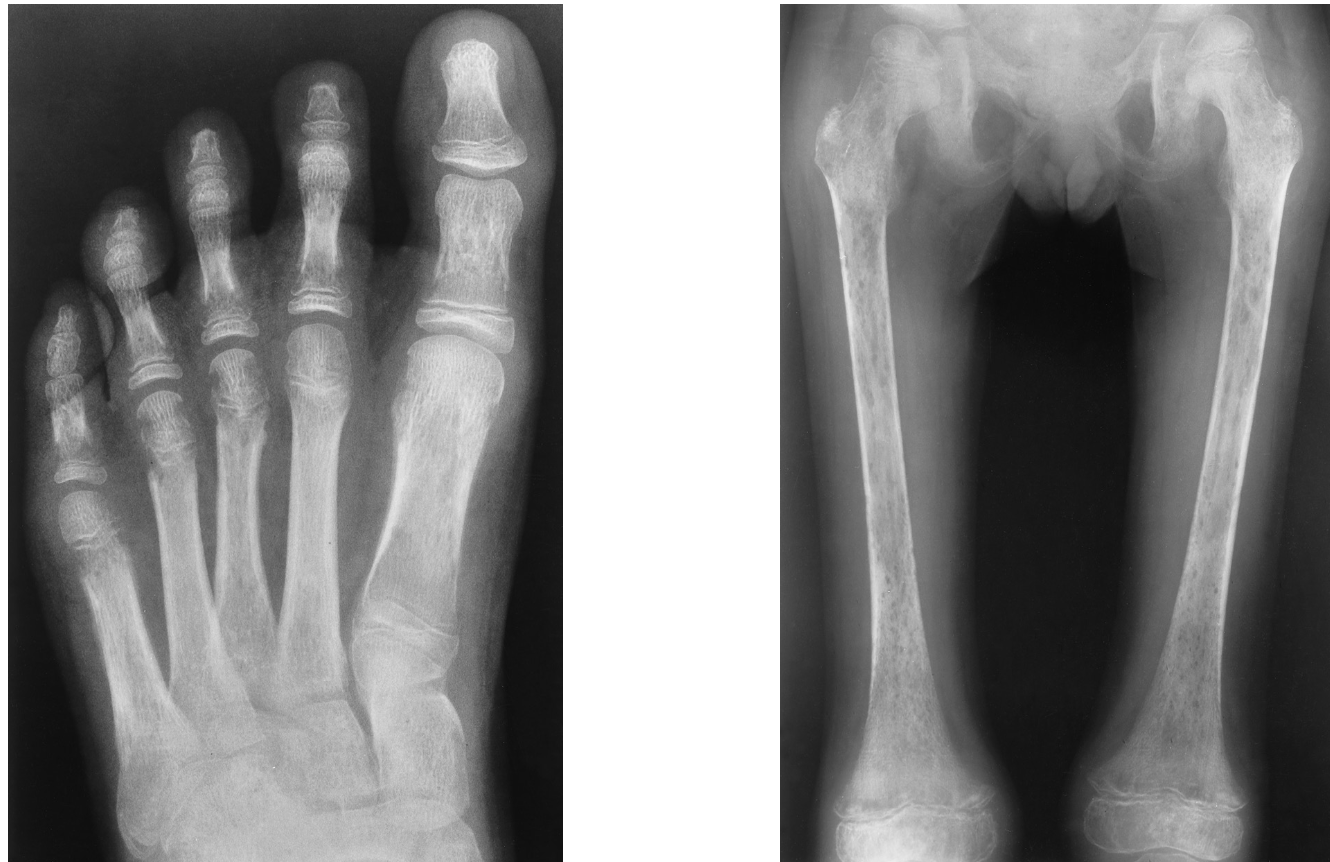

transverse radiolucent bands at the metaphyseal ends of long bones “moth-eaten”

leukemia radiographically